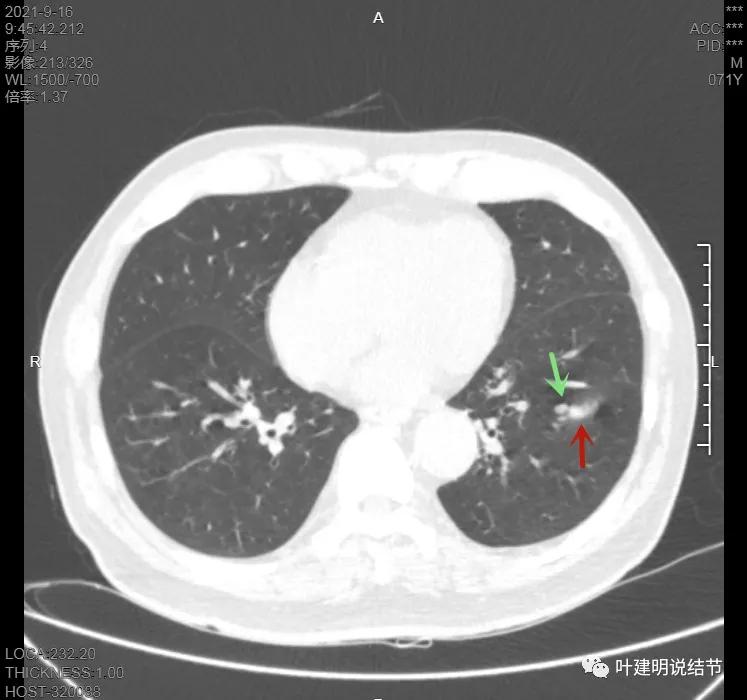

上图示病灶在左下叶,红色所指的与绿色箭头所指的是两个病灶,不相连的,实性结节